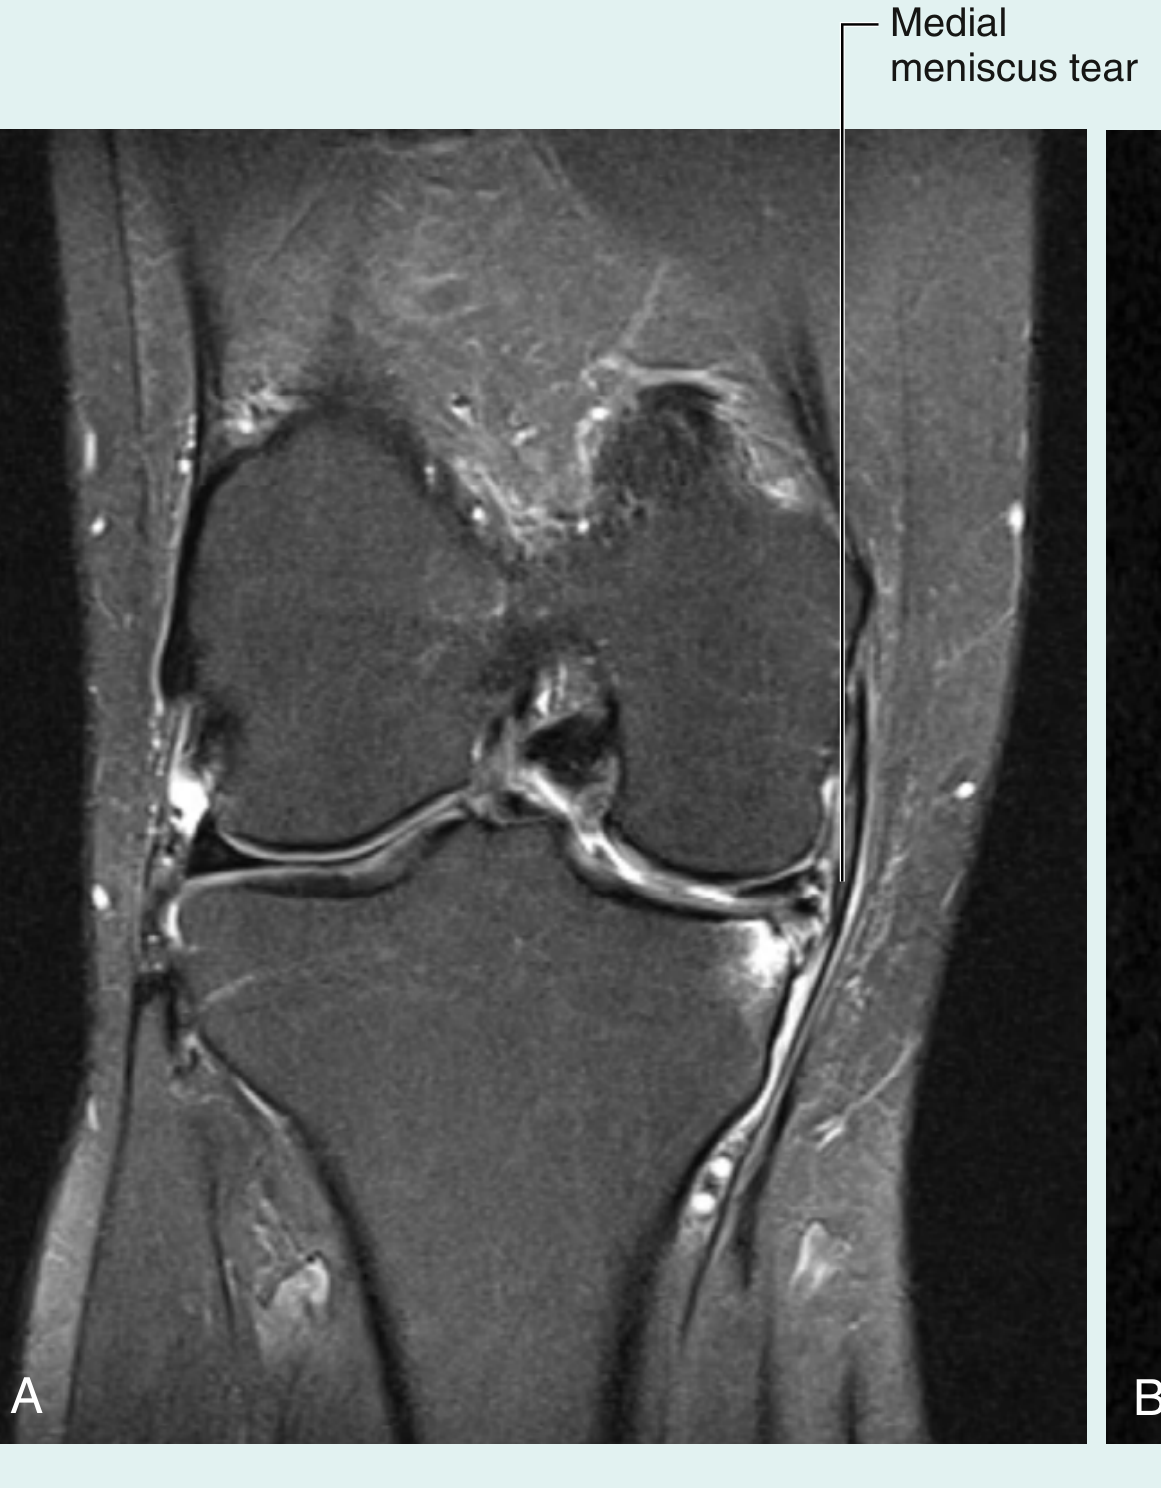

Coronal MRI showing medial meniscus tear

Coronal MRI of the knee showing a medial meniscus tear (Gray's Anatomy for Students)

Fragment-in-Notch Sign (Coronal)

Displaced dark low-signal fragment sitting in the intercondylar notch; peripheral meniscus appears truncated.

Coronal MRI — flipped bucket-handle fragment of medial meniscus within the intercondylar fossa (arrow); peripheral meniscus is truncated

Bucket-handle tear — fragment-in-notch sign, coronal view (Grainger & Allison's Diagnostic Radiology)

Coronal MRI — displaced bucket-handle fragment (arrowhead) in the intercondylar notch beneath the cruciate ligaments

Bucket-handle tear — "fragment-in-notch" sign (PMC)